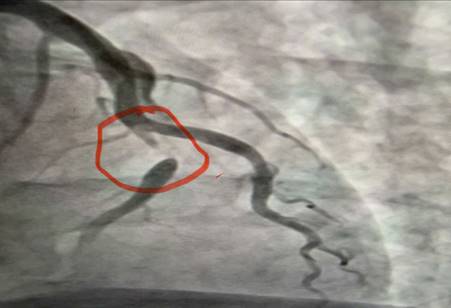

Hình ảnh động mạch vành tái thông sau can thiệp

Ê-kíp bác sĩ khoa Nội tim mạch đã tiến hành chụp động mạch vành kết quả cho thấy: nhánh động mạch thủ phạm gây Nhồi máu cơ tim cấp là đoạn 1 động mạch liên thất trước hẹp 95%. Bệnh nhân đã được can thiệp nong và đặt Stent động mạch vành giúp tái thông dòng máu nuôi tim, hạn chế tối đa tổn thương cơ tim và các biến chứng nguy hiểm. Sau can thiệp mạch vành tái thông tốt, tình trạng người bệnh ổn định, các triệu chứng đau ngực giảm rõ rệt và tiếp tục được theo dõi, điều trị theo phác đồ chuyên môn.